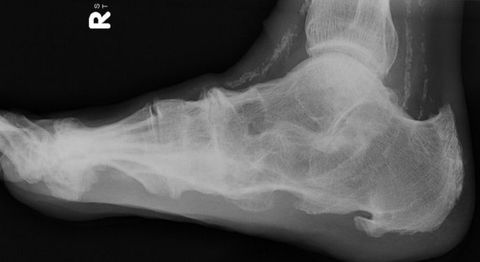

| What disease is this? What does the arrow indicate? | Rheumatoid arthritis. Arrow = Bone erosion secondary to inflammation of retrocalcaneal bursa. |

| What disease is this? What does the arrow show? | Non-articular psoriatic arthritis Arrow = 'fluffy spur' |